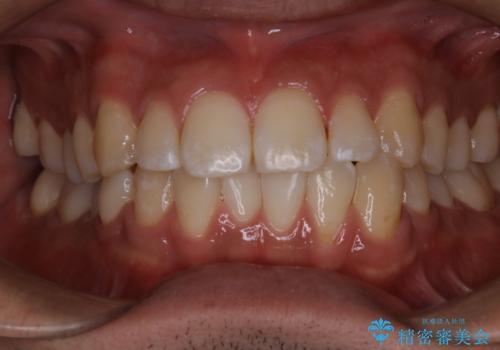

- コーヒーを毎日飲むので、どうしても着色がついてしまう。前歯の目立つ着色をきれいにとってほしいとのことでした。

PMTC60分コースを行いました。

PMTCは、歯に付着した汚れを除去していくため、着色が気になる場合にも行うことができます。ご自身でのセルフケアだけで着色を落とそうとすると、逆に歯を傷つけてしまったり、精密に汚れを除去できないこともあります。また、日常生活で着色しやすい飲食物を避けたりすることはストレスに感じてしまったり、あまり現実的ではありません。

歯科医院にて、適切な処置を行うことで、長期的に安定したお口の環境が作られます。まずはカウンセリングなどもおススメです。